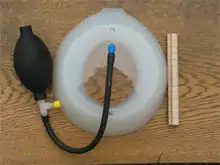

Vacuum bell

An alternative to surgery, the vacuum bell, was described in 2006; the procedure is also referred to as treatment by cup suction. It consists of a bowl shaped device which fits over the caved-in area; the air is then removed by the use of a hand pump.[33] The vacuum created by this lifts the sternum upwards, lessening the severity of the deformity.[34] It has been proposed as an alternative to surgery in less severe cases.[35] Once the defect visually disappears, two additional years of use of the vacuum bell is required to make what may be a permanent correction.[36][37] The treatment, in combination with physiotherapy exercises, has been judged by some as "a promising useful alternative" to surgery provided the thorax is flexible; the duration of treatment that is required has been found to be "directly linked to age, severity and the frequency of use".[38][39] Long-term results are still lacking.[35][38][39]

A single-center study reported in the Journal of Pediatric Surgery found that use of vacuum bell therapy resulted in an excellent correction in twenty percent of patients, but "is not a substitute for the Nuss procedure which can achieve an excellent result in 90% of patients".[40] Variables predictive of an excellent outcome include age ≤ 11 years, chest wall depth ≤ 1.5 cm, chest wall flexibility, and vacuum bell use over 12 consecutive months.[40]

In an article by Interactive Cardiovascular and Thoracic Surgery, the results found that vacuum bell treatment is safe for correcting the deformity non-surgically. The treatment has been shown to have higher success rates in patients who present earlier, have a mild and/or symmetrical deformity, a flexible chest wall and lack of costal flaring.[41]

The vacuum bell can also be used in preparation to surgery.[35][39]